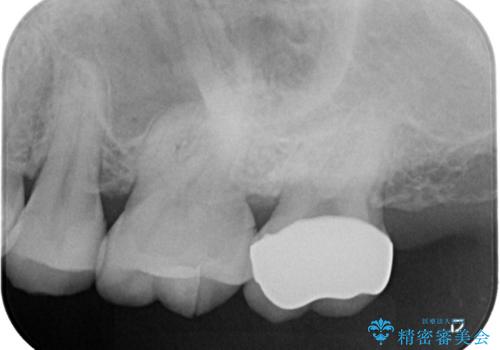

- レントゲンにて昔入れたインレーの下に虫歯が見つかった患者様です。

歯髄に近接する虫歯でしたが、根管治療は必要なくクラウンにて修復を行うことができました。